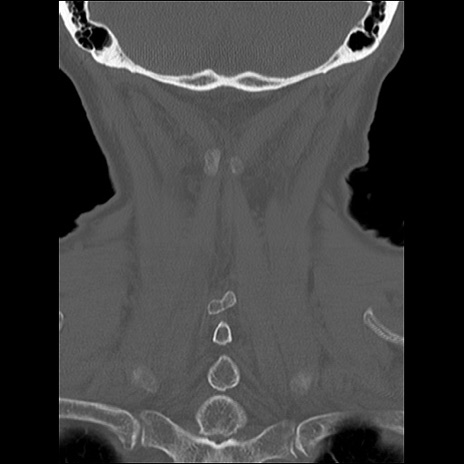

症例48 頚椎CT(冠状断像)

頚椎CT